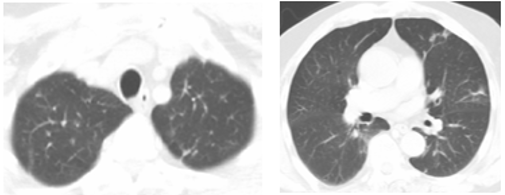

图:治疗前,肺部多发转移

(蓝箭头标出)

图:治疗后,病灶几乎完全消失